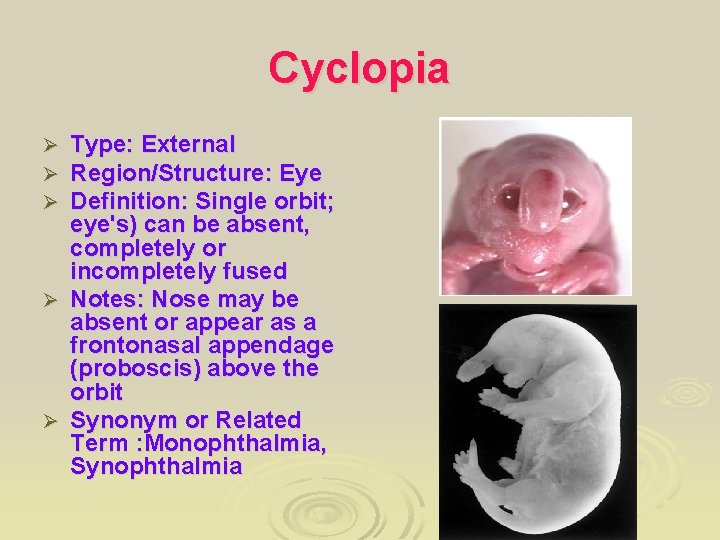

Cyclopia Type: External Region/Structure: Eye Definition: Single orbit; eye's) can be absent, completely or incompletely fused Ø Notes: Nose may be absent or appear as a frontonasal appendage (proboscis) above the orbit Ø Synonym or Related Term : Monophthalmia, Synophthalmia Ø Ø Ø